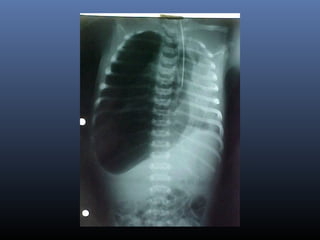

 Achados radiológicos:

Quadros leves:

Infiltrados em formas de estrias.

Pequenos nódulos

Hiperinsuflação pulmonar

Quadros moderados e graves:

Infiltrações nodulares grosseiras e

difusas.

Áreas de hiperinsuflação alternadas

com áreas de atelectasia.

Síndrome de Aspiraçãode Mecônio  Achados radiológicos: Quadros leves: Infiltrados em formas de estrias. Pequenos nódulos Hiperinsuflação pulmonar Quadros moderados e graves: Infiltrações nodulares grosseiras e difusas. Áreas de hiperinsuflação alternadas com áreas de atelectasia.